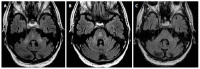

We describe common and less common diseases that can cause magnetic resonance signal abnormalities of middle cerebellar peduncles (MCP), offering a systematic approach correlating imaging findings with clinical clues and pathologic mechanisms. Myelin abnormalities, different types of edema or neurodegenerative processes, can cause areas of abnormal T2 signal, variable enhancement, and patterns of diffusivity of MCP. Pathologies such as demyelinating disorders or certain neurodegenerative entities (e.g., multiple system atrophy or fragile X-associated tremor-ataxia syndrome) appear to have predilection for MCP. Careful evaluation of concomitant imaging findings in the brain or brainstem; and focused correlation with key clinical findings such as immunosuppression for progressive multifocal leukoencephalopahty; hypertension, post-transplant status or high dose chemotherapy for posterior reversible encephalopathy; electrolyte disorders for myelinolysis or suspected toxic-drug related encephalopathy; would yield an appropriate and accurate differential diagnosis in the majority of cases.